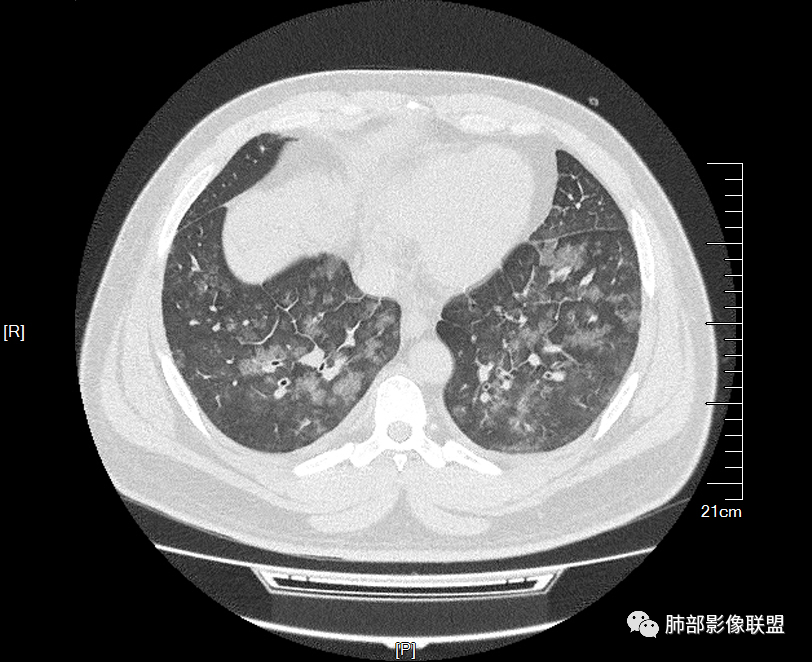

双肺多发弥漫性磨玻璃结节影,大小不一,形态不规则,部分融合,支气管未见明显扩张,部分血管束略增粗,叶裂胸膜增厚,临床有痛风,左足痛6天,考虑:1:痛风结节(一般实性结节,很少磨玻璃结节影)2:血管炎?3:病毒性肺炎(水痘-疱疹肺炎?)

双肺多发腺泡结节及磨玻璃,小叶间隔增厚(大网格状),腺泡结节内及磨玻璃内可见细网格影(小叶内间隔增厚),影像表现符合肺泡出血改变,血肌酐升高,考虑肺肾综合征。鉴别肺水肿。

两肺弥漫向心分布的腺泡结节,部分融合,两肺小叶间隔增厚,血肌肝高,考虑肺泡性肺水肿

年轻男性,既往血肌酐升高,左足痛六天入院,有痛风及高血压病史。CT示双肺多发磨玻璃结节影,不规则,部分融合成团或片状,小叶间隔增厚,以双下肺为明显,叶间胸膜亦见增厚。考虑为1.Good-Pasture综合征。2.病毒性肺炎?3.肺水肿?

男32岁。既往曾发现血肌酐升高.此次因左足痛6天入院。有痛风、高血压病史。两肺弥漫性的病变,小片状或者结节状为主病变,小叶中心分部为主,边界不清。心影比较饱满,肝实质密度均匀的降低。考虑为肝损害的影像学改变。综合考虑多功能脏器的损害,肺部损害肺泡炎?肺水肿?或病毒性的肺炎?

年轻男性,有痛风、高血压病史,有肾功不全史。双肺弥漫性分布磨玻璃样结节,部分融合,无重力分布,考虑1.血管炎。2.肺肾综合征。3.肺水肿。

年轻男性,痛风史,高血压史,肌酐高,左足痛6天入院。胸CT:双肺多发弥漫性磨玻璃结节影,大小不一,部分融合,上中下肺都有,中内带多,胸膜下少。部分血管束略增粗,小叶内间隔、小叶间隔增厚,下肺明显,左室大。叶裂胸膜增厚。临床有痛风,左足痛6天,考虑:心衰、间质性肺水肿?弥漫性肺泡出血?鉴别:MPA,肺肾综合征,痛风结节等。

青年男性,有肾功能不全史和痛风史,这个影像分布有个典型的特点,全部是以中央间质周围的渗出性改变,这个改变主要就是两种可能,一种是肾功能不全导致的血管通透性增高导致的肾性肺水肿,一种是出血导致的DAH改变,具体是哪种,影像上不好简单的鉴别,需要结合更多临床资料综合分析。

年轻男性,痛风,肌酐高,提示肾功能有损,两肺多发磨玻璃腺泡结节,小叶间隔增厚,双侧少许胸水,血管增粗,考虑肾性肺水肿,DAD,鉴别肺肾综合征,需要更多临床资料

双肺多发腺泡结节及斑片状磨玻璃影,边缘不清,后者内见细网格状改变,小叶间隔增厚,呼吸系统症状不明显,考虑肺水肿,过敏性肺泡炎代排

32岁男性,左足痛入院。有痛风、肌酐升高、高血压病史。CT:两肺弥漫磨玻璃结节,小叶间隔增厚、小叶内间质增厚,两侧少量胸水。考虑:1.肺水肿;2.过敏性肺炎;3.肿瘤?

双肺多发腺泡结节及磨玻璃网格影,部分融合,小叶间隔增厚,双肺中轴间质增厚不明显,疾病谱:病毒性肺炎,肺泡出血,水肿,过敏性,肺泡蛋白沉着症,PCP。结合病史,没有咳血,肺泡出血,不考虑,过敏没有任何临床症状,而且无上肺分布优势,也排除。病毒性肺炎也无临床支持,排除。PAP影像不典型,暂排除。有肾功能异常,所以考虑1肾源性肺水肿。2,有无激素使用史或HIV,PCP待排。

青年男性,双肺多发大小不等斑片状磨玻璃密度影,内见细网格影,并可见小叶间隔增厚,双侧胸腔少量积液,患者曾有血肌酐增高,提示曾有肾损害,并有痛风、高血压病史,考虑肺肾综合征,鉴别过敏性肺炎

多发GGO结节,边界清,以全小叶、小叶中心为主:

GGO背景

小叶间隔增厚,无明显重力趋势

少量积液,脂肪肝

这里有一点重力趋势

中轴间质稍增厚

细网格也明显

中轴间质增厚,小叶间隔增厚,小叶内间质增厚,部分重力作用,双侧对称,胸水,按理淋巴道回流受阻有

肺水肿类病变有

问题是腺泡结节如何解释?